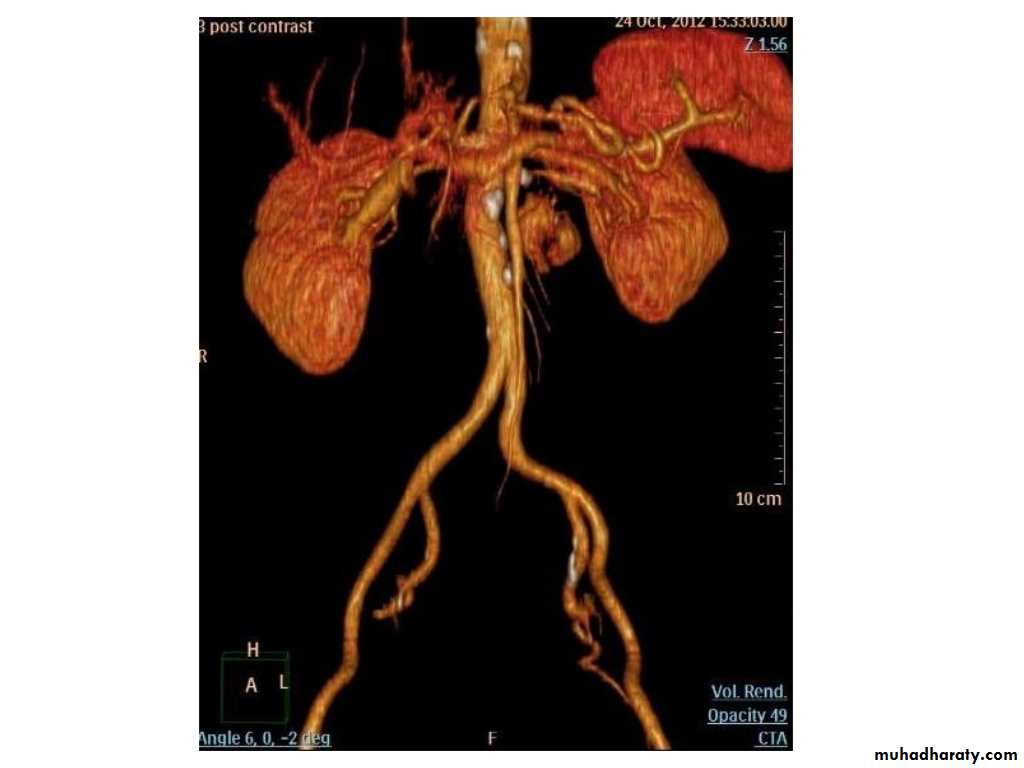

IVU shows

1. The kidneys at low position .2.Close to the spine with long axis parallel to the spine

3. Malrotation manifested by medially directed calyces.

4- The renal pelvis and ureters are anterior and lateral in position.

5- Hydronephrosis and calculi highly associated.